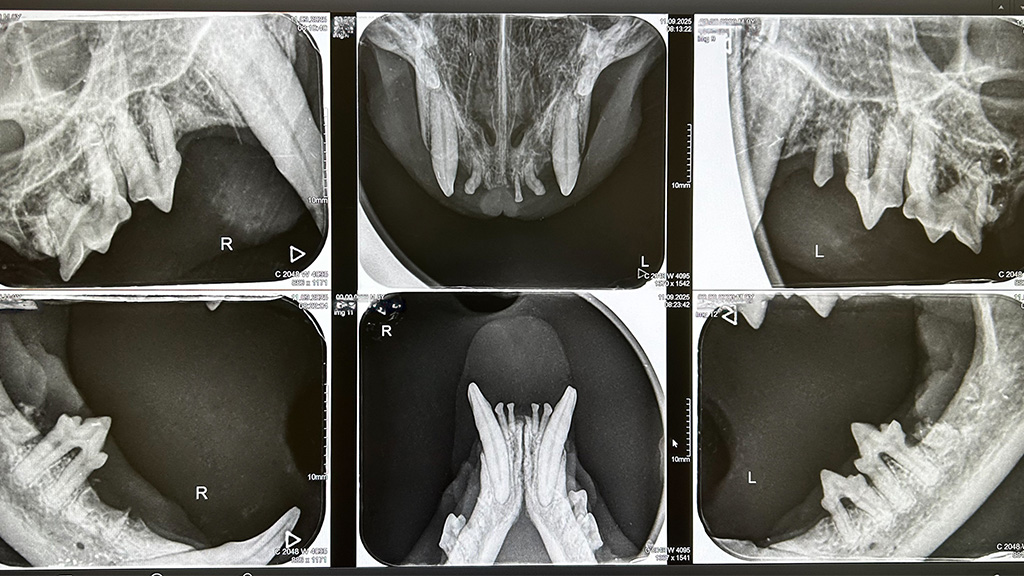

Digitales Zahnröntgen

Das Dentalröntgen erfolgt mit einem speziellen Röntgengerät und erlaubt eine präzise Darstellung von Zahn, Zahnwurzel und Kiefer. Die optimale Diagnose und Therapie von unterschiedlichsten Zahn- und Kieferproblemen ist nur in Verbindung mit dem Zahnröntgen möglich (z.B. FORL der Katze). Ohne die Röntgenuntersuchung bleiben diese oft lange unerkannt. Die Folgen sind vermeidbare Schmerzen sowie ein Fortschreiten der Erkrankungen.